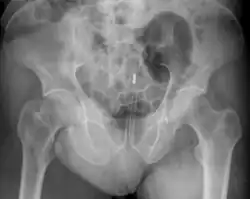

Een lichaamsvreemd voorwerp in de endeldarm is een via de anus ingebracht voorwerp, dat soms zonder medische hulp niet meer verwijderd kan worden.

Hulpverlening